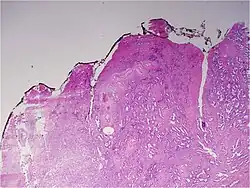

Gleason pattern 3. H&E stain.

• Pattern 3 – The tissue still has recognizable glands, but the cells are darker. At high magnification, some of these cells have left the glands and are beginning to invade the surrounding tissue or having an infiltrative pattern. This corresponds to a moderately differentiated carcinoma.

Gleason 3

Gleason 3 is a clearly infiltrative neoplasm, with extension into adjacent healthy prostate tissue. The glands alternate in size and shape, and are often long/angular. They are usually small/micro-glandular in comparison to Gleason 1 or 2 grades. However, some may be medium to large in size. The small glands of Gleason 3, in comparison to the small and poorly defined glands of pattern 4, are distinct glandular units. Mentally you could draw a circle around each of the glandular units in Gleason 3.[4][7]